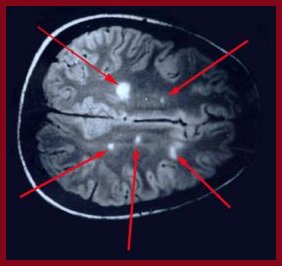

Case Patient’s B12 Deficiency Causes Chiasmal Lesion

Graph (MRI/MRA) of the brain, which found no sign of compressive pernicious anemia. Vitamin B 12 deficiency may exist without hema-tological manifestations. The cause chiasmal lesions; demyelinating disease, vasculitis and ... Get Document

Cient due to underlying pernicious anemia Magnetic resonance imaging (MRI) of the brain was unremarkable. MRI signal throughout on T2-weighted images, with patchy areas of punctate en-hancement. Axial images indicated that the lesions were in the posterior region (Fig. 1 ... Read Document